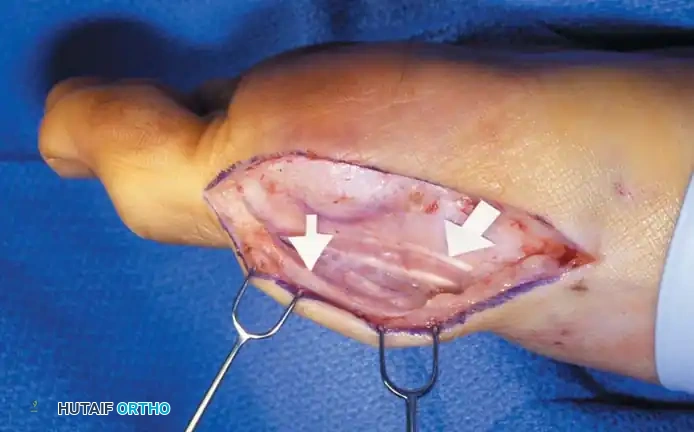

Keller Resection Arthroplasty The Keller procedure combines resection hemiarthroplasty of the fi rst metatarsophalangeal joint with removal of the medial eminence of the fi rst metatarsal (Fig. 78-28). Although removing the base of the proximal phalanx decompresses the joint and mobilizes the hallux, allowing marked correction of valgus, the varus of the fi rst metatarsal is not corrected, and maintaining correction of the valgus of the hallux is diffi cult. Other complications of the Keller procedure have been emphasized in the literature to such an extent (with neither the incidence nor the severity of such complications clearly documented) that the indications for this procedure have been limited severely. In our experience, however, complications are uncommon if patients are selected carefully. Modifi cations in the original technique also have allowed expansion of the indications for the Keller bunionectomy. Candidates for the Keller procedure are patients older than 50 years with moderate-to-severe hallux valgus (30 to 45 degrees); intermetatarsal angles of 13 degrees or less, indicating mild-to-moderate metatarsus primus varus; and pain over the medial eminence with any shoe worn, so the variety of shoes the patient can wear is severely limited. An incongruous fi rst metatarsophalangeal joint caused by

Fig. 78-26 Modifi ed McBride bunionectomy (DuVries; Mann). A, Medial capsule of second metatarsophalangeal joint is sutured to lateral capsule of fi rst metatarsophalangeal joint with interposition of released adductor hallucis. B, Medial capsular resection. C, Confi guration after capsular resection. D, After capsular imbrication, hallux should rest in neutral position or not exceed 5 degrees of varus. E, Postoperative dressing technique (Mann). ( E after Beverly Kessler; courtesy of LTI Medica and The Upjohn Company.) lateral subluxation of the phalanx on the metatarsal head, severe lateral displacement of the sesamoids, and any evidence of degenerative cartilage changes in the joint all are radiographic indications for the Keller procedure. Two modifi cations in technique can expand these indications, however, to include patients with more severe deformities (Fig. 78-29) (but not to include younger patients): fi bular sesamoidectomy and lateral displacement of the fi rst metatarsal. Using these modifi cations, Donley et al. obtained an average 18-degree correction of the metatarsophalangeal angle and an average 6-degree correction of the intermetatarsal angle in 38 patients (50 feet);

95% of patients were satisfi ed with their results. Patients with 50 degrees or more of valgus of the hallux (18 to 20 degrees of varus of the fi rst metatarsal), complete lateral dislocation of the sesamoids, marked degenerative changes, and severe pronation of the hallux may benefi t functionally and cosmetically from alterations of the standard technique.

Fig. 78-29 Severe hallux valgus with bursa formation in 70-year-old woman. A and B, Anteroposterior and lateral clinical photographs of patient’s right foot. C, Correction of deformity by modifi ed Keller procedure. D, Preoperative and postoperative weight bearing radiographs of same patient.

The following modifi cations of the Keller technique can expand the indications for use with more severe deformities.

REMOVAL OF THE FIBULAR SESAMOID

• When the medial eminence and phalangeal base have been excised, remove the fi bular sesamoid.

• Place a sturdy two-toothed retractor beneath the metatarsal head, and have an assistant lift it dorsally.

• Using a Freer elevator or a small osteotome for its strength, mobilize the fi bular sesamoid (Fig. 78-31A to C). This may be diffi cult in elderly patients with signifi cant deformity and adherence of the sesamoid to the metatarsal head. Lift the metatarsal dorsally for exposure (Fig. 78-31D and E).

• When the sesamoid is mobile, identify the fl exor hallucis longus tendon by placing traction on the hallux and fl exing and extending the interphalangeal joint of the hallux. The tendon is visible just distal to and in alignment with the sesamoids, which straddle it.

• Identify and expose the lateral neurovascular bundle just lateral to the tendon by blunt dissection.

• Pull the plantar medial capsule medially. This requires a fi rm grasp on the capsule. The medial traction brings the intersesamoid “ligament” into better view.

• Incise the intersesamoid ligament longitudinally with a No. 67 Beaver or No. 15 Bard-Parker blade. If tenotomy scissors are used, place one arm of the scissors under the ligament (this arm rests on the dorsal side of the fl exor hallucis longus) and the other arm dorsal to the ligament.

• When the intersesamoid ligament is incised, grasp the sesamoid fi rmly with forceps or a small Kocher clamp, fl ex the toe at the interphalangeal and metatarsophalangeal joints to relax the fl exor hallucis longus tendon, and pull the fi bular sesamoid distally and medially.

• With release of the intersesamoid ligament, the medial surface of the fi bular sesamoid is free from soft tissue. Distally, the sesamoid is free because of resection of the base of the proximal phalanx. This leaves two sides of the sesamoid, distal and medial, free of soft tissue.

• While pulling the sesamoid distally and medially, use a small blade to incise along the lateral margin of the sesamoid under direct vision. Keep pulling the head of the metatarsal dorsally and holding the hallux distracted and in fl exion. This greatly aids in identifi cation of the margins of the fi bular sesamoid, particularly laterally and proximally.

• The most diffi cult part of the sesamoidectomy and that which should be done last is release of the proximal lateral corner of the sesamoid where the fl exor hallucis brevis lateral head inserts. While incising the lateral capsular attachments to the sesamoid, do not bury the blade of the knife because the neurovascular bundle to the lateral side of the hallux is just lateral to the capsule.

• Now all attachments to the fi bular sesamoid have been removed except the lateral head of the fl exor hallucis brevis, which inserts on the proximal lateral margin of the sesamoid. This is a diffi cult section to remove; however, this section can be released under direct vision by pulling the sesamoid distally and medially and lifting the metatarsal head dorsally with a strong two-toothed retractor.

• When the sesamoid has been removed, insert two 0.062-inch Kirschner wires retrograde from the tip of the toe 2 to 3 mm plantar to the nail bed, leaving about 5 to 7 mm of the pins exposed at the base of the phalangeal remnant to help align the phalanx on the metatarsal before antegrade passage of the pins into the metatarsal (Fig. 78-31F).

Fig. 78-31 Excision of fi bular sesamoid in modifi ed Keller procedure. With base of proximal phalanx removed and medial eminence excision, exposure of fi bular sesamoid is not as diffi cult from medial incision. A, Operative photograph showing elevation of fi rst metatarsal with strong two-tooth retractor and use of small osteotome to mobilize fi bular sesamoid and lateral capsuloligamentous (frequently contracted) structures. Osteotome is between metatarsal head and lateral sesamoid. When mobilization of fi bular sesamoid is complete, entire sesamoid is visible for excision. Note chondromalacia of tibial sesamoid articular surface medial to osteotome. B, Fibular sesamoid has been excised, and lateral capsular structures and conjoined tendon (in forceps) have been released. Neurovascular bundle to lateral side of hallux is adjacent to these structures. C, Diagrammatic representation of modifi ed Keller procedure. By excising fi bular sesamoid, valgus moment of conjoined tendon of fl exor hallucis brevis and adductor hallucis no longer pulls fl exor hallucis longus tendon laterally (carrying hallux with it) through capsulosesamoid plantar plate and pulley system. D, Metatarsal head must be lifted dorsally to excise fi bular sesamoid under direct vision. E, Note exposure of fi bular sesamoid after mobilization of metatarsal head. Continued